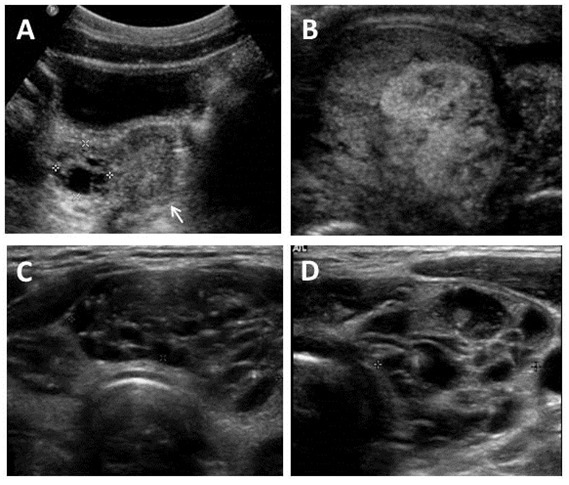

Figura 4. Imágenes ecográficas en el Síndrome de McCune-Albright

A. Ecografía pélvica en una niña de 7 años mostrando un quiste ovárico complejo unilateral (delimitado por las cruces). El útero tiene un tamaño prepúber (flecha).

B. Ecografía testicular en un adulto mostrando una lesión heterogénea con elementos mixtos sólidos y quísticos.

C&D. Hallazgos tiroideos ecográficos típicos del Síndrome de McCune-Albright incluyendo la apariencia heterogénea y quística (de “queso suizo”).

Es muy frecuente en niñas con DF/MAS (~85%). Es habitual que la pubertad precoz sea el síntoma inicial de la enfermedad. Los quistes ováricos recurrentes (Ver Figura 4A) conlleva la producción intermitente de estrógenos lo cual resulta en el desarrollo de senos, aceleración del crecimiento lineal y sangrado vaginal. Durante los intervalos entre la involución de quistes antiguos y la formación de quistes nuevos, el tejido mamario suele involucionar y los niveles de estrógeno sérico retornan a niveles prepuberales. El desarrollo de quistes ováricos suele continuar en la edad adulta, por lo que es frecuente que las pacientes afectas presenten ciclos menstruales irregulares (Lala et al 2007). La torsión ovárica se ha descrito en raras ocasiones en niñas y mujeres con quistes persistentes de gran tamaño (Clark et al 2000).

Las alteraciones testiculares están presentes en la mayoría de varones con MAS (~85%), y típicamente se manifiestan como macroorquidismo unilateral o bilateral (Boyce et al 2012a). La exploración ecográfica suele mostrar discretas lesiones hiper e hipoecoicas así como microlitiasis, las cuales corresponden a áreas de hiperplasia de células de Leydig y/o Sertoli (Ver Figura 4B).

La afectación de la glándula tiroides es muy frecuente en los pacientes con DF/MAS. Se detectan alteraciones ecográficas tiroideas en aproximadamente la mitad de los individuos con DF/MAS. Estas alteraciones incluyen la presencia de lesiones mixtas solido-quísticas y lesiones sólidas entremezcladas con áreas de tejido de apariencia normal. (Figura 4C y 4D) (Celi et al 2008, Tessaris et al 2012a).